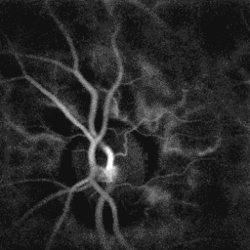

- Fluorescein angiography is a helpful adjunct. Findings include delayed venous filling, hypofluorescence caused by hemorrhage and capillary nonperfusion, dilation and tortuosity of veins, leakage due to neovascularization and macular edema.